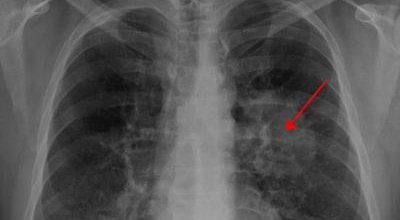

폐암 검사는 X-ray를 통해서 검사하는데 , 크기가 작거나 구석에 위치한 경우 확인이 어려운 경우도 있답니다. 그리고 조직 검사를 통해서 정확한 진단을 하게 돼요. 폐암이 발견되면 종양의 크기나 전이 여부 , 위치에 따라서 수술 여부를 결정하게 돼요.